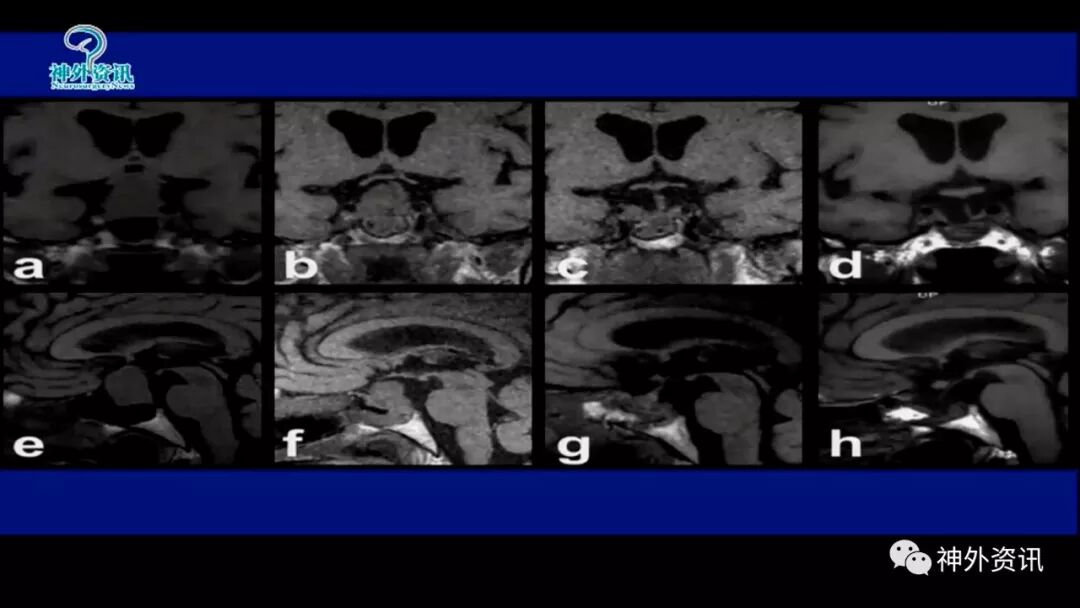

垂体巨大腺瘤经鼻蝶显微切除术

鞍上型—经鼻蝶垂体微腺瘤切除术